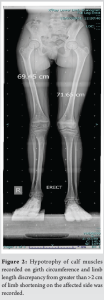

We present an 11-year-old girl with a painful anterior right thigh swelling for 4 years. It began as a painful small lump deep in her anterior mid-thigh region and gradually progressed to a large swelling that caused her severe local pain and limitation of movements at the knee. Her mother noticed a limp with pelvis and shoulders dropping to the affected side while walking and this has progressed over the past year. She had undergone an incisional biopsy which was inconclusive and treated with intra-lesional chemical/sclerosant injection before presentation to our institution. Our clinical evaluation brought to light a deep intramuscular soft-tissue neoplasm in the anterior thigh muscles which was tender on palpation and was limiting her knee mobility with range 10°–40° possible on active and passive examination (Fig. 1). Hypotrophy of calf muscles recorded on girth circumference and limb length discrepancy from >2 cm of limb shortening on the affected side was recorded (Fig. 2).